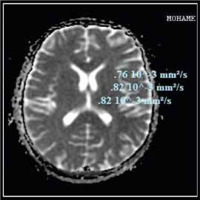

Compared to the control group, the ADC values of cirrhotic patients with HE were significantly higher. There were no significant differences between cirrhotic patients with MHE and those with overt HE in different brain regions. As shown in Table 5 and Figures 3 and 4, there was no statistically significant difference in ADC values between brain regions.

Fig. 3

Apparent diffusion coefficient (ADC) values in different brain regions of a patient with cirrhosis and minimal hepatic encephalopathy (MHE)